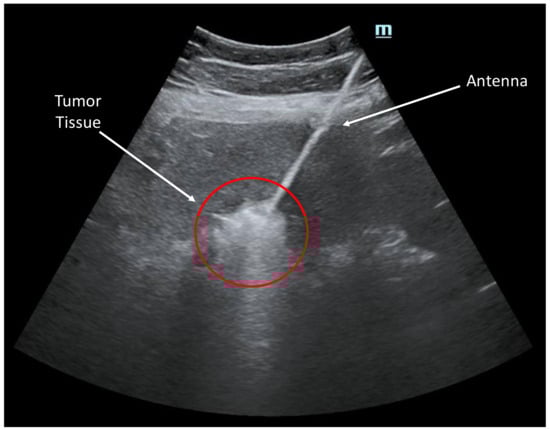

The Emprint microwave ablation system and Emprint antenna were selected based on the characteristics of the target lesion. The system was prepared, ensuring proper functioning and calibration. Power and treatment time parameters were set based on the size and location of the lesion. Anesthesia was administered according to the patient’s needs and the physician’s discretion, which could involve local anesthesia or conscious sedation. Under ultrasound image guidance (Figure 3), the antenna was accurately positioned within the target lesion. The optimal insertion point and trajectory were determined, followed by a percutaneous insertion of the antenna using a minimally invasive approach, guided by real-time imaging. Once the antenna was in place, the microwave ablation system was activated to deliver the predetermined power and treatment time. The ablation process was carefully monitored to ensure proper tissue heating within the targeted region. If necessary, adjustments were made to the antenna position to achieve complete coverage of the lesion.

Figure 3. Ultrasound image showcasing an ablation procedure in progress. The image captures the targeted area where a catheter was guided to deliver precise energy to remove abnormal tissue. Real-time visualization provided by ultrasound technology allowed for accurate placement of the catheter, ensuring optimal treatment efficacy.